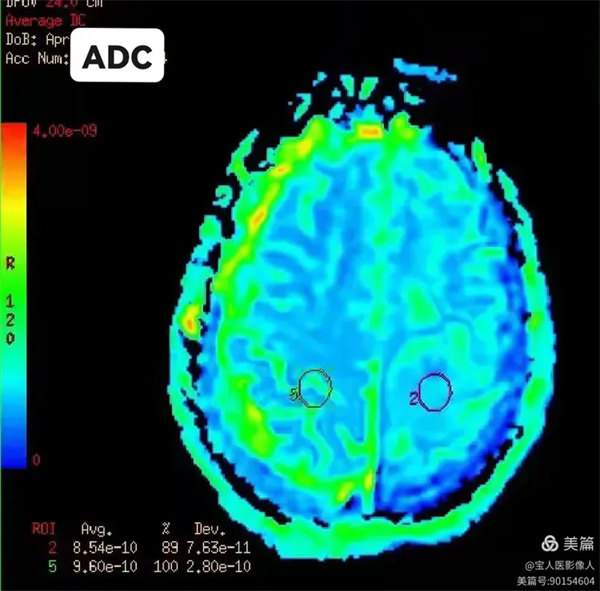

圖4:部分各向異性指數(FA)

病灶局部的各向異性指數值。(圖左下角顯示測量數值)

圖6:容積比(VRA):

病灶與相應正常對照側腦組織容積比數值對照。